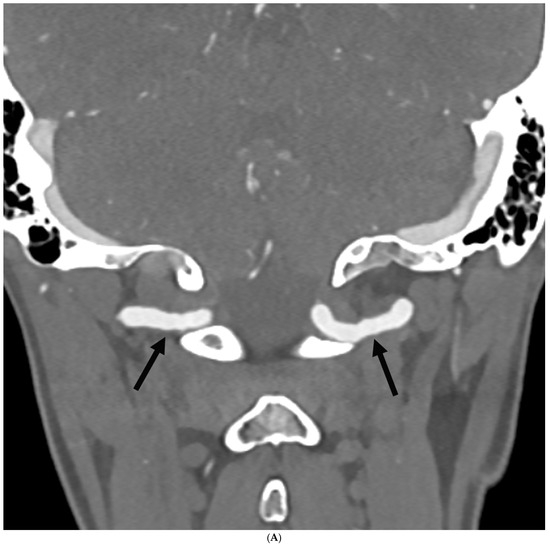

Prevalence of Intracranial and Cervical Artery Abnormalities in Patients with Hypermobile Ehlers–Danlos Syndrome and Hypermobility Spectrum Disorders Presenting to an Academic Headache Clinic

by Todd D. Rozen, Katelyn A. Bruno, Ethan M. Rozen, Frances C. Wilson, Marysia S. Tweet, Raymond C. Shields, Sharonne N. Hayes, Dacre R. T. Knight, Shilpa N. Gajarawala, Sukhwinder J. S. Sandhu, Alok A. Bhatt and DeLisa Fairweather

Neurol. Int. 2026, 18(2), 33; https://doi.org/10.3390/neurolint18020033 - 11 Feb 2026

Background/Objective: It remains unknown whether patients with the more common forms of hypermobility carry an elevated risk for the development of intracranial/cervical artery abnormalities. The objective of this study was to determine the prevalence of unruptured intracranial aneurysms, spontaneous cervical artery dissections, and fibromuscular dysplasia in patients with hypermobile Ehlers–Danlos Syndrome (hEDS) and hypermobility spectrum disorders (HSD) who presented to an academic headache clinic. Methods: This is a retrospective cohort study. We used an electronic medical record to look for all patients seen at the Mayo Clinic Florida Headache Center and EDS Clinic between 2019 and 2025 with a diagnosis of hEDS or HSD and neuroimaging of both the intracranial and cervical arteries. Results: There were 103 patients who met the inclusion criteria. There was no statistically significant difference between hEDS and HSD patients in developing cerebral/cervical arterial anomalies. Of the sample, 95% of the hypermobile patients with abnormal neuroimaging also had migraine. A total of eleven (10.7%) patients (hEDS + HSD) were diagnosed with unruptured intracranial aneurysms. Trends included age less than 50 years, small aneurysms in the anterior circulation, and having migraine with aura. Five (4.8%) patients were diagnosed with spontaneous cervical artery dissection with trends for HSD, over the age of 50 years, vertebral artery involvement and a history of migraine without aura. Six (5.8%) patients were diagnosed with fibromuscular dysplasia with trends for HSD, over the age of 50 years, carotid artery involvement and a history of migraine with aura. Conclusions: This is the first study to identify that patients with the more common type of EDS, HSD and hEDS, and a possible concomitant history of migraine have a heightened risk for the development of unruptured intracranial aneurysms, spontaneous cervical artery dissections, and fibromuscular dysplasia. Our findings suggest the need for targeted screening with intracranial and extracranial arterial imaging for this unique patient population. Full article